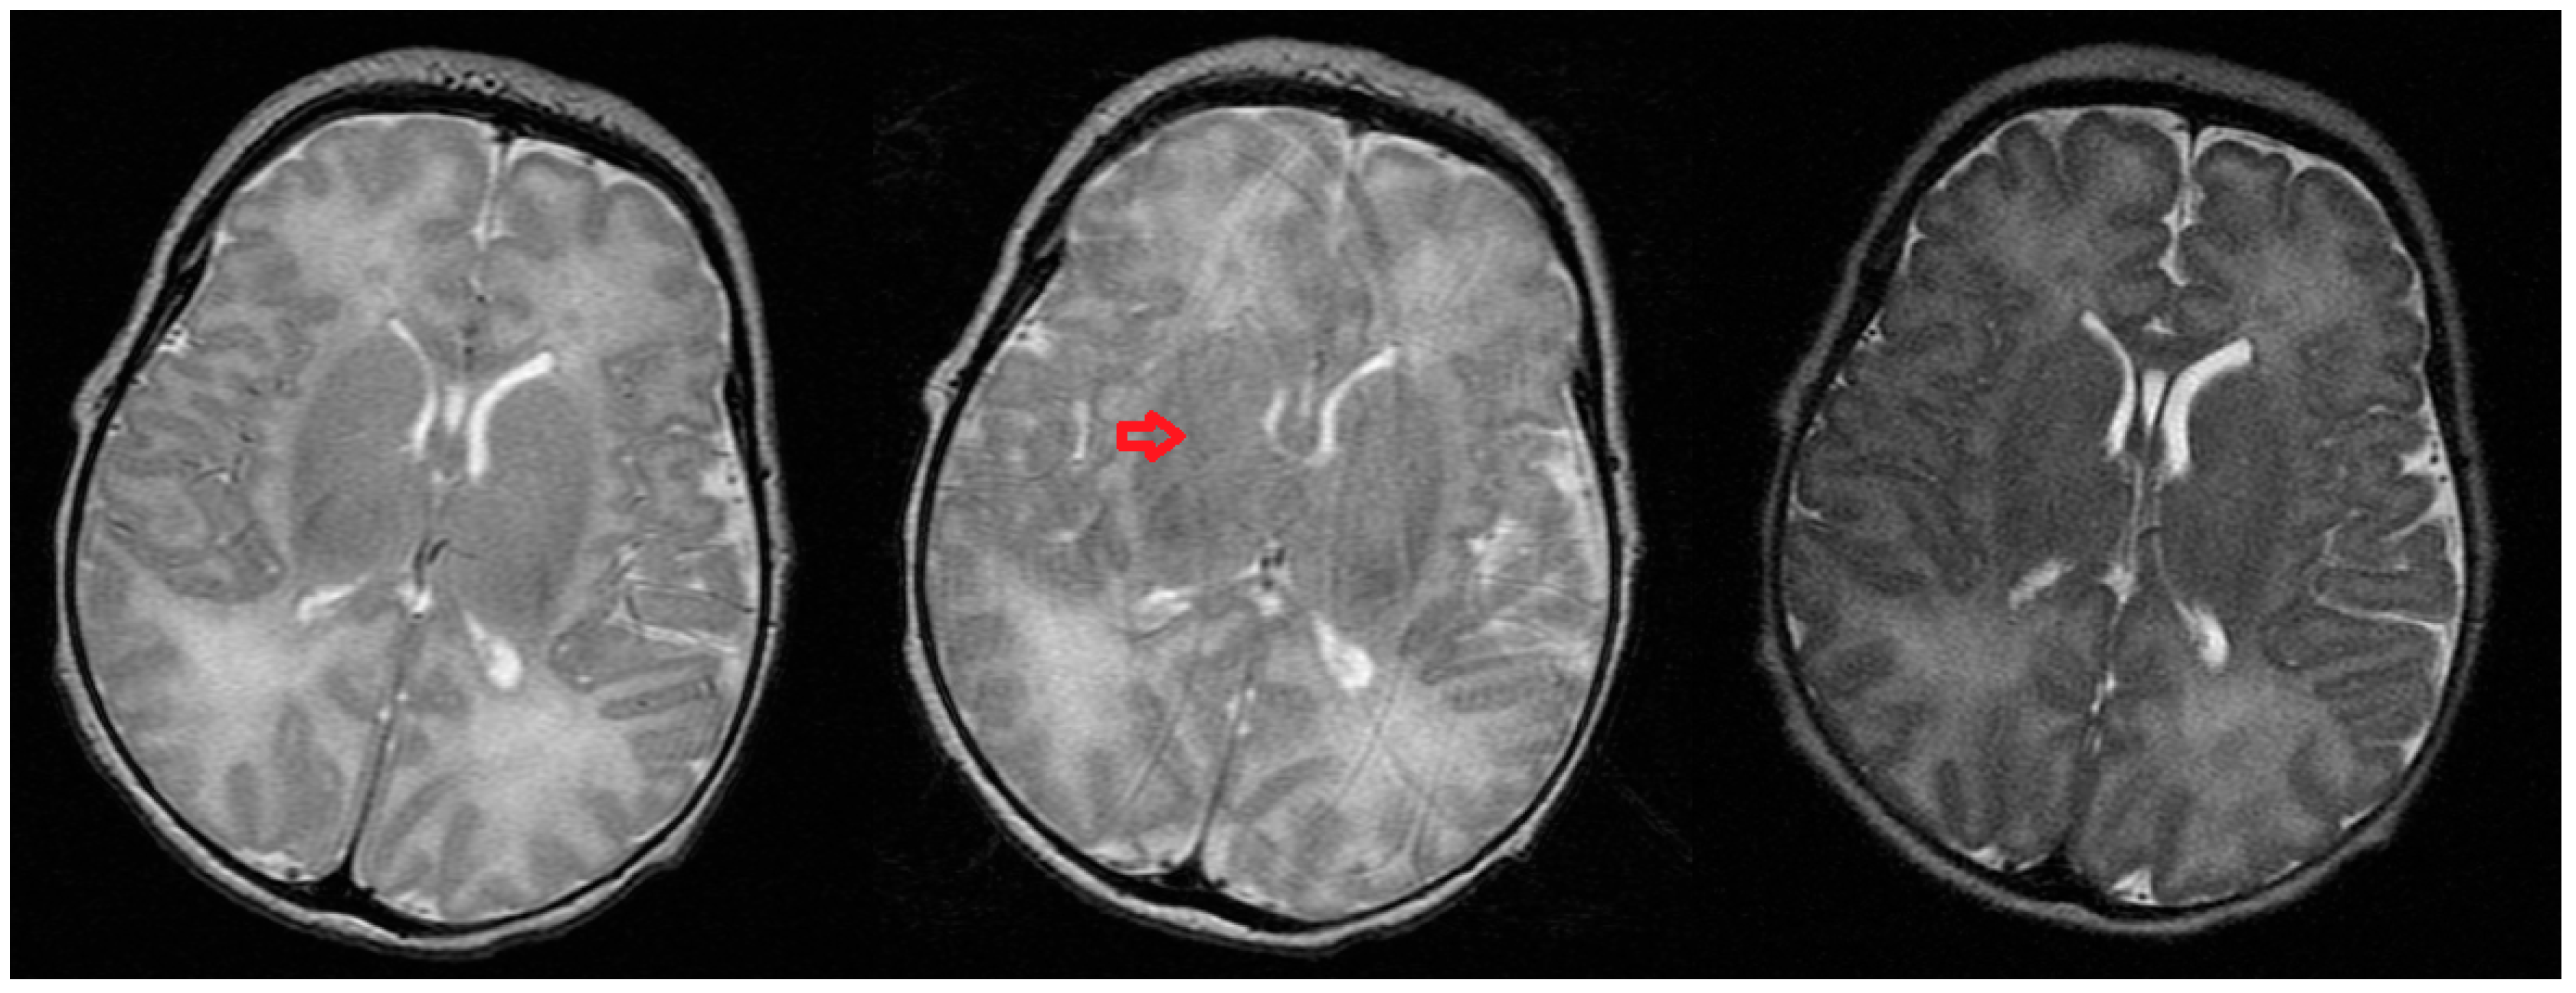

In Figure 7, Figure 8 and Figure 9 the effects of correcting MR k-space data of the test object acquired on the dedicated 3T Neonatal MRI system with simultaneously acquired wireless accelerometer data are shown for cases of both weak and strong angular motion. Some weak non-planar motion is observed in the beta and gamma channels in Figure 7a, despite best attempts to keep the motion restricted to one-plane. Figure 7b shows the result of down-sampling the alpha channel (axial in-plane rotation) of the wireless accelerometer to match the corresponding phase encode steps in time. The resultant averaging of the signal improves the signal to noise ratio of the angular measurements. The previously measured angular calibration of the accelerometer was used to convert the measurements into radians.

An example of relatively weak axial in-plane rotational motion of the test object (shown static in Figure 8a) is shown in Figure 8b, corresponding to the wireless accelerometer measurements shown in Figure 7b. The peak-to-peak angular variation was ~5 × 10−2 radians through the MR acquisition, similar to the simulation shown in Figure 6b. No artifacts from the radiofrequency or gradient pulses of the MR system are seen on the accelerometer traces. As the measurement is made totally independently from the MR scanner, there was no MR acquisition time penalty incurred. An attempt to correct the image motion artifact is shown in Figure 8c. Careful inspection of the internal segmental structure of the orange (dark lines) shows some subtle improvement in signal intensity assignment.

Figure 8. MR images of an orange acquired on the 3T neonatal MRI system with no in-plane angular motion (a) and pseudo-sinusoidal in-plane rotational motion about the iso-centre; (b) corresponding to the measurements shown above in Figure 7; (c) an attempt to remove the motion using the measured rotation angles shows some subtle improvement of image quality.